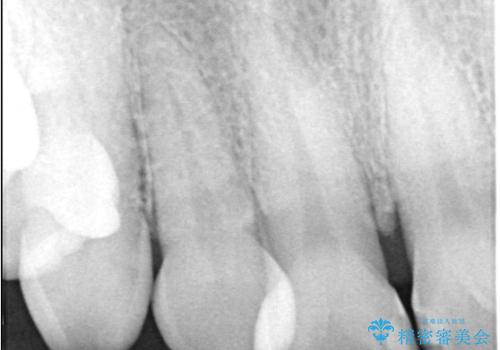

そのため今回は、右上2番を抜歯し、右上1番および左上1番をオールセラミッククラウンで審美的に修復しました。

矯正によって歯並びや咬み合わせを整えた後、必要に応じて歯の形や色を整えるためにホワイトニングやセラミック治療を行うことで、より自然で美しい仕上がりが期待できます。

治療期間も短く、抜歯からわずか3か月でオールセラミッククラウンを装着することができます。